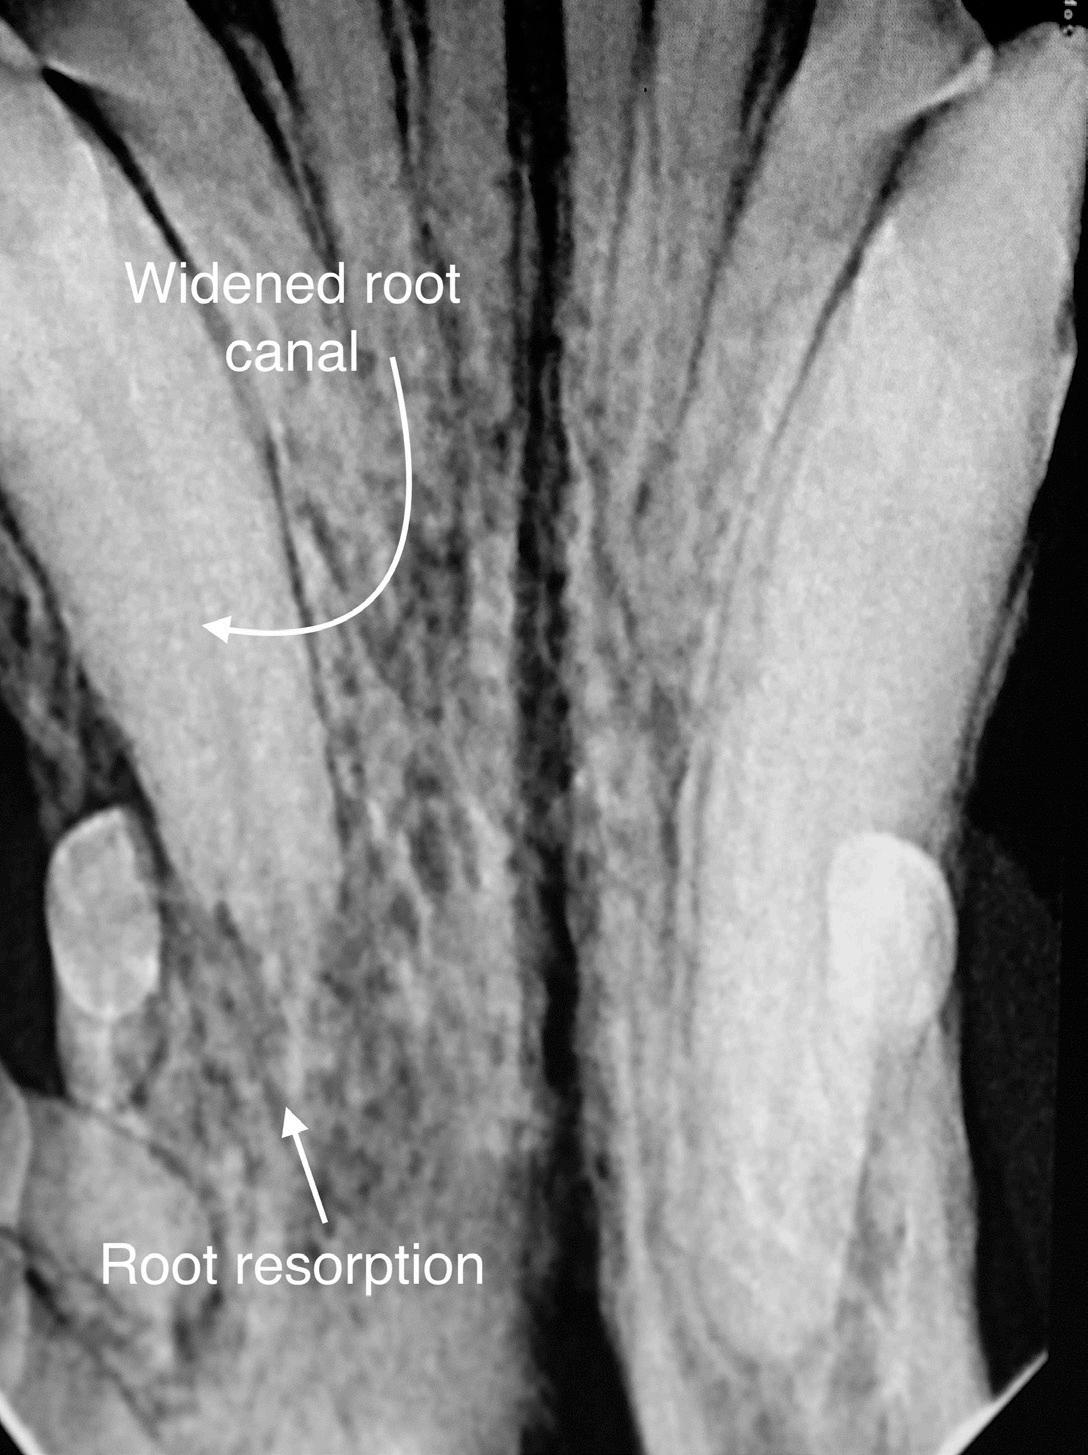

• Abnormalities in the root canal, such as obstruction, resorption, or enlarged canal(s) compared to adjacent teeth.

• Periapical pathology, such as widened periodontal ligament space at the tooth's apex and circumscribed alveolar bone resorption. In the early stages of endodontic disease, bony changes are not radiographically present. As the infection progresses, a homogeneous radiolucency at the apex or a dark halo in the periapical tissues becomes apparent, typical of an infection. A sharply outlined circumscribed radiolucent area is commonly caused by a periapical cyst, which usually arises from preexisting granulomas.

Figure 6: Right maxillary second incisor enlarged root canal and periapical lucency consistent with endodontic disease. Image courtesy of Dr. Jan Bellows. Figure 7A: Fractured left mandibular canine with pulp exposure and periapical lucency. Figure 7B: Periapical lucencies surrounding the three roots of the right maxillary fourth premolar. Figure 7C: Pulp exposure and periapical lucencies consistent with apical granulomas affecting a dog’s left mandibular first molar. Image courtesy of Dr. Jan Bellows.